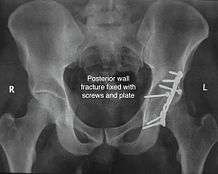

Posterior wall fracture

This is the most common variety of fracture

Treatment: if the femur head is dislocated, it should be reduced as soon as possible, to prevent damage to its blood supply. This is preferably done under anaesthesia, following which, leg is kept pulled by applying traction to prevent joint from dislocating.

The final management depends on the size of the fragment(s), stability and congruence of the joint.

If the fragments do not fall into place, or if there are bone pieces in the joint, or if the joint is unstable, surgical fixation using screw(s) and plate(s) is performed

Post-surgery treatment: depending on the stability achieved, the person may be allowed standing and walking with help of support for about six to eight weeks.

Full function may return in about three months.